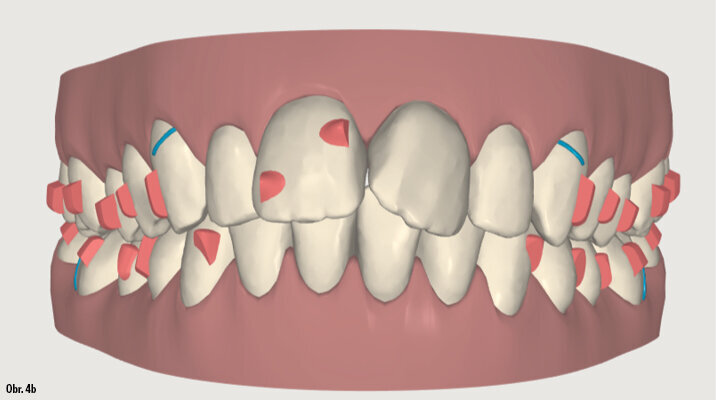

25letá pacientka požadovala estetickou ortodontickou léčbu, kterou nebylo jednoduché naplánovat vzhledem k tomu, že je umělkyní a cestuje po celé Evropě. Během vyšetření byla diagnostikována II. třída 1. oddělení, mírné stěsnání v dolní čelisti a středně těžké stěsnání v čelisti horní. Incizální schůdek byl 10 mm. Profilová zkouška jasně ukazuje protruzní postavení rtů (obr. 1a–c). Pacientka odmítla extrakční nebo ortodonticko-chirurgickou léčbu. Vhledem k jejím požadavkům na estetiku byl léčebný plán stanoven takto: léčba fóliovými aparáty Invisalign (Align Technology) s výsledným postavením molárů i špičáků v I. třídě, které bude dosaženo postupnou distalizací horních molárů s pomocí kompozitních attachmentů na všech distalizovaných zubech a tahů II. třídy (obr. 2, 3). Pacientce bylo doporučeno nosit fólie a tahy II. třídy nejméně 21 hodin denně. Dále pacientka používala přístroj AcceleDent 20 minut denně po celou dobu trvání ortodontické léčby. Fólie byly měněny každé 2 týdny, dokud nebyly druhé horní moláry plně distalizovány, potom každých 10 dnů, dokud nebyly první moláry ve své finální pozici, a nakonec každých sedm dní až do konce léčby.

ClinCheck (Align Technology) software navrhl k získání požadovaných výsledků 63 alignerů s předepsaným množstvím atachmentů a nasazením tahů II. třídy. Odhadovaná doba léčby byla přibližně 30 měsíců. Nicméně protože se pacientka rozhodla používat přístroj AcceleDent, léčba byla ukončena již po 18 měsících bez nutnosti refinementu, tedy s původně plánovanými 63 alignery (obr. 4a–c, 5a–c).

Klinický výsledek byl vynikající, postavení molárů i špičáků v I. třídě, vyhovující překus a předkus. I profil dolní třetiny obličeje byl výrazně lepší.

Na překrytí kefalometrických snímků je zřejmá distalizace molárů o 6 mm bez výraznějšího sklonu a s ideálním bukolingválním sklonem řezáků. Tahy druhé třídy umožnily protrakci mandibuly o 1,5 mm. Jako retenční aparáty jsme zvolili Vivera retainery (Align Technology) (obr. 6, 7a–c, 8a–c).